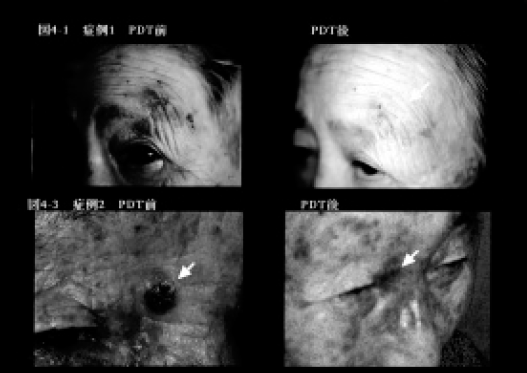

1)日光角化症 66~93歳の女性の顔面にみられた日光角化症に対してPDTを行った。図3-1には82歳女性のPDT 前の所見を示した。

2)菌状息肉症 1例の菌状息肉症(62歳、女性)の体幹に多発する紅斑性浸潤局面(図4-1)に対してPDTを試みた。

20%5 - aminolevulinic acid(5-ALA)含有軟膏を密封塗布(6h)。ハロゲンランプ(500W)にて20分間(120J/cm2)照射した。

日光角化症では1~5回の照射で1週後に皮疹は1~6週で消失(図3-2)、菌状息肉症では2回の照射により4週後には色素沈着を残すのみとなった(図4-3)。6カ月後の現在いずれも再燃をみていない。日光角化症の一例でPDT後のアポトーシス発現を検討した結果(Apotosis Detection Kit、宝酒造使用)、PDT 施行部にアポトーシス陽性細胞が観察されたが、染色態度は均一でなく、なお慎重な検討が必要と思われた。